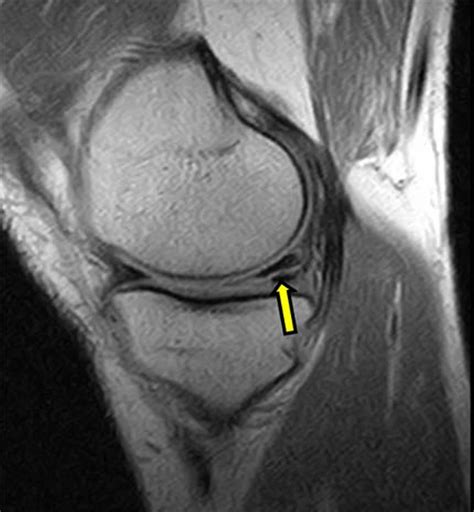

When looking at Torn Meniscus MRI pictures, the goal is to identify signal abnormalities within this cartilage structure. Healthy menisci appear as dark, triangular shapes on standard MRI sequences. When a tear is present, it disrupts this dark signal, allowing bright fluid or scar tissue to show up in the image.

• T1-weighted images: Excellent for showing anatomy. The meniscus appears very dark.

• T2-weighted images: Sensitive to fluid. Since joint fluid is bright on T2, this sequence helps detect tears because the fluid enters the tear, making it “light up.”

• Proton Density (PD): Often the best sequence for viewing the meniscus, providing a high level of detail to distinguish between healthy tissue and internal tears.

Radiologists are trained to scrutinize the meniscus for specific patterns of signal intensity. A healthy meniscus should have low signal intensity (meaning it looks black on the MRI). A torn meniscus typically exhibits increased signal intensity (appearing white or bright) within the substance of the cartilage.

However, it is important to note that not all bright signals are tears. Sometimes, age-related degeneration can cause internal signal changes that do not actually represent a structural tear that requires surgery. A tear is definitively diagnosed when the high-signal intensity extends to the articular surface of the meniscus. When you see this on an MRI, it confirms that the cartilage has been compromised.

• Horizontal Tear: Often related to degeneration; it splits the meniscus into top and bottom halves.

• Longitudinal/Vertical Tear: Usually caused by trauma; it runs parallel to the outer edge of the meniscus.